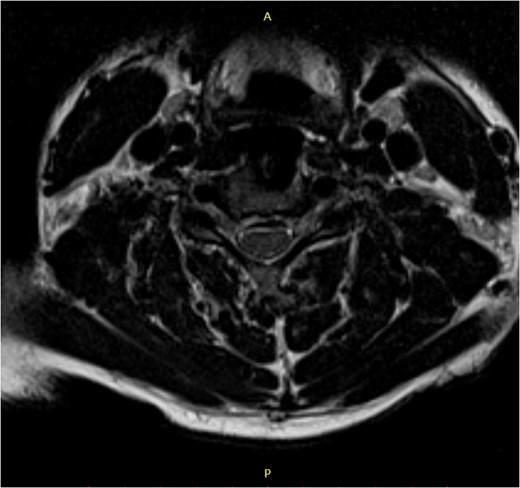

The patient's symptoms ceased in the early postoperative period. The neurological examination results were normal within a month (Nurick Grade: 0; Chile's mJOA: 16 points; recovery rate (RR) 91.6%). Patient was followed-up for 5 years.